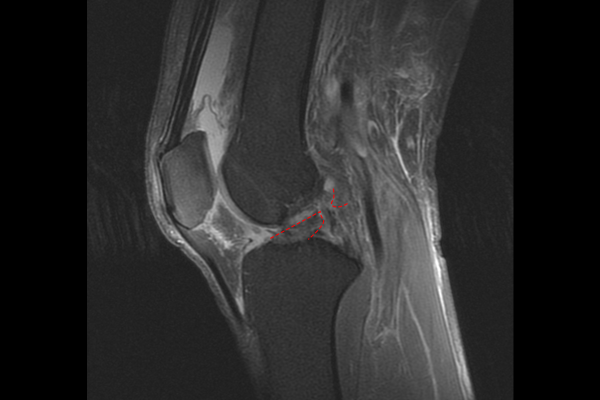

55세 남성 환자분께서 우측 무릎 통증 및 불안정함 증상으로 내원해주셨습니다. 환자분께서는 내원 전날 넘어지면서 무릎이 다치셨다고 말씀하셨고, 걸을 수는 있는데 휘청거리면서 불안정하다고 하셨습니다. 특히 높은 계단에서 내려올 때, 버스에서 내릴 때 무릎이 빠질 것 같은 느낌이 들었다고 말씀하셨습니다.

환자분의 병력을 들으며, 신체검진을 했을 때, 무릎 전방전위 검사, 라크만 검사(Lachman test)에서 양성 반응을 확인하였고, 정확한 무릎 상태 파악을 위해 MRI 검사를 진행하였습니다. MRI 검사 결과 전방십자인대가 파열되어 연결성이 없는 것을 확인하여 우측 무릎 전방십자인대파열(Rt. knee ACL rupture)을 진단하였습니다.